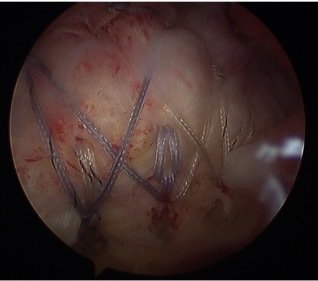

This piece of research based on Mr Patel's work at the EOC was presented at the ISAKOS congress in Shanghai, China on 4 June 2017. An abstract of the paper can be found here.